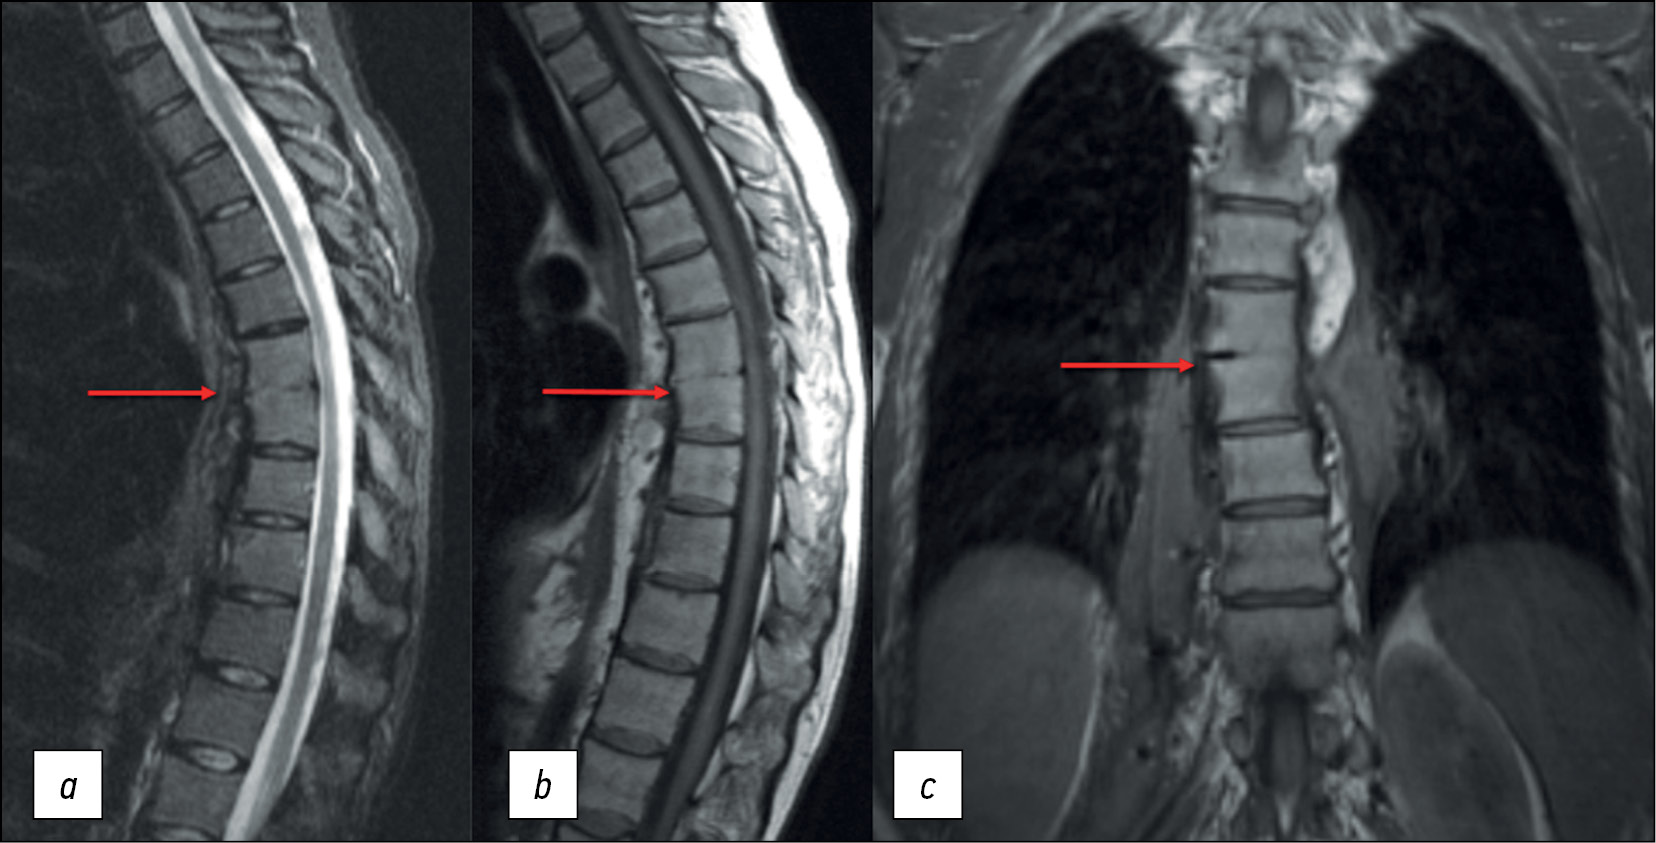

The patient is a 42-year-old female. Back pain and lumbar fistula complaints initially appeared 3 yr ago. According to the medical history, the patient received spinal anesthesia for a cesarean section 6 months prior. The patient experienced fistula relapses approximately three to five times a year. At the presentation, a magnetic resonance imaging (MRI) revealed bony and fibrous ankylosis ТhVII–ТhVIII (Figure 1), which could indicate both spondylitis in remission and contact spinal infection.

Fig. 1. Thoracic spine MRI: (а) STIR mode, sagittal plane; (b) T1WI mode, sagittal plane; and (c) T1WI mode, coronal plane. The arrows indicate bony and fibrous ankylosis ТhVII–ТhVIII.

A follow-up thoracic and lumbar spine MRI performed in the hospital revealed stable changes in the ТhVII–ТhVIII vertebral bodies and bilateral paravertebral abscesses (Figure 4).

Fig. 4. Thoracic and lumbar spine MRI: T2WI mode, coronal plane. Bony and fibrous ankylosis ТhVII–ТhVIII and paravertebral abscesses (arrows) on the left (а), with air bubbles on the right (b).